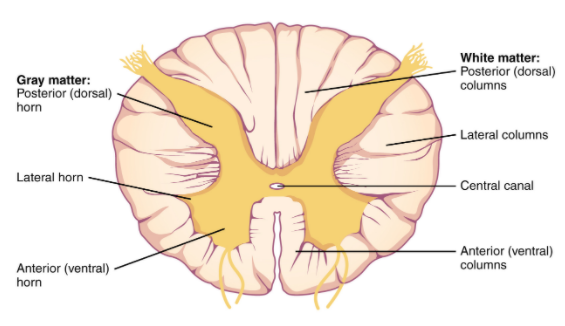

The spinal cord is divided into four different sections (the cervical, thoracic, lumbar, and sacral regions) and it consists primarily of two types of tissue: grey matter and white matter (grey matter being cell bodies and white matter involving a lot of myelinated neuronal fibers passing down through the spinal cord).

It is approximately 43-45 cm (18 inches) long in adults, with a diameter ranging from 13 mm (1⁄2 inch) in the cervical and lumbar regions to 6.4 mm (1⁄4 inch) in the thoracic area. The center of the spinal cord is hollow and contains a structure called central canal, through which cerebrospinal fluid flows (this helps to clear waste and provide nutrients).

A cross section of the spinal cord. Source: Vedantu

The spinal cord is covered by a protective membrane called ‘meninges’. Note that the outer layer of meninges is referred to as the dura mater. The space between the surrounding vertebrae and the dura mater is called the epidural space (This it important in relation to the rest of the post). Administration of anaesthesia into the epidural space can cause a loss of sensation, by blocking the transmission of signals through nerve fibers in or near the spinal cord. As such, “epidurals” are commonly used for pain relief during childbirth and surgery.